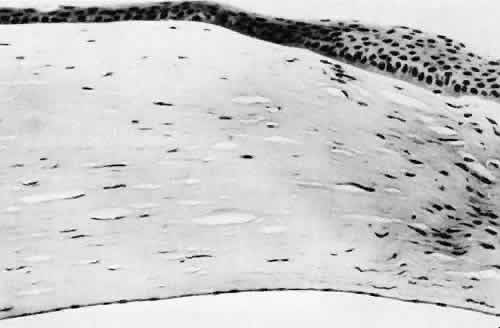

Fig. 5. Collagen lamellae retract when cut, causing the wound to gape when incised. If the extent of the incision is limited, as in clear cornea cataract incisions, the gaping may be countered by swelling of corneal stroma exposed to aqueous media. (Hematoxylin-eosin stain; × 100.)

Fig. 6. Descemet's membrane (D) has elastic properties that cause inward curling when incised. The fibrous reaction between cut ends of Descemet's membrane indicate a wound of long standing. (PD stain; × 100.)